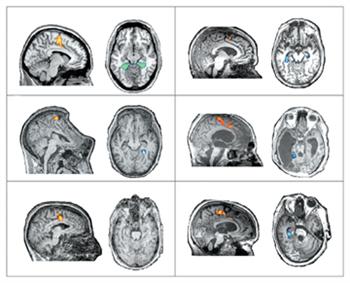

Os doentes em estado vegetativo que não podem mexer-se, nem falar para transmitir o que sentem, poderão conseguir comunicar. Revela um estudo publicado no New England Journal of Medicine.

«Um grupo de cientistas conseguiu estabelecer comunicação com pacientes em estado vegetativo, em que estes respondiam mentalmente “sim” ou “não” às perguntas dos investigadores.»